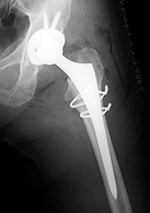

| Total hip arthroplasty with cerclage wires |

| |

The cerclage wires were placed because a femoral shaft fracture (not visible herein) occurred during the prosthesis placement. There is subcutaneous gas from recent placement of the prosthesis. From Taljanovic, 2005 |